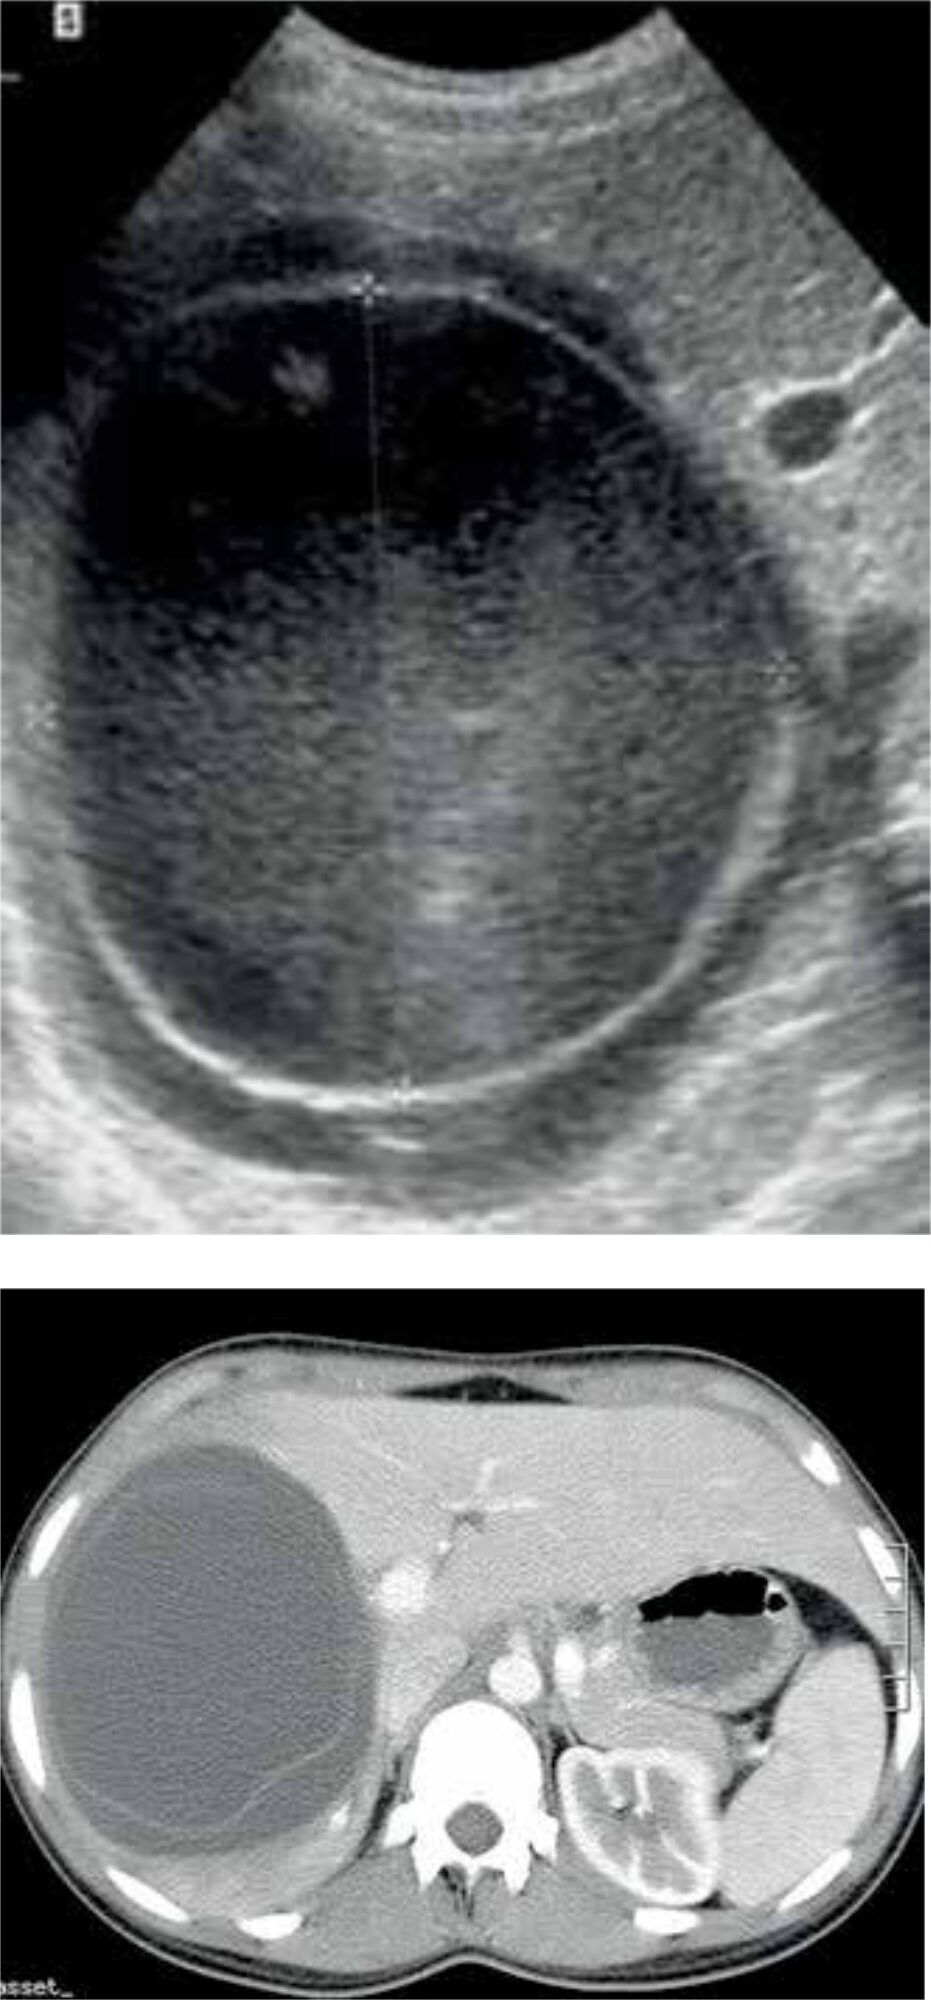

A combination of epidemiological and clinical findings, serological and immunological tests, and imaging is used to confirm the diagnosis of CE. Serology is helpful in detecting CE, but as a result of an undetectable immune response it misses about 30-40% of cases. Furthermore, many endemic countries lack the resources to use serology as a diagnostic tool. [11] Therefore, ultrasonic imaging is seen as the cornerstone in diagnosing CE. The accuracy is almost 90%, depending on the experience of the clinician. [12] Alternatively, a CT- or MRI-scan may be performed (Figure 4). [11]

Two classifications have been developed, based on ultrasound: the Gharbi and the WHO 2001 classification. The latter is a modification of the Gharbi classification made by the WHO Informal Working Group on Echinococcosis (WHO-IWGE); [13] it is recommended as the imaging reference standard, for guiding treatment and for use in follow-up (Table 1).

| I | CE 1 | Univesicular fluid collection/simple cyst | Active |